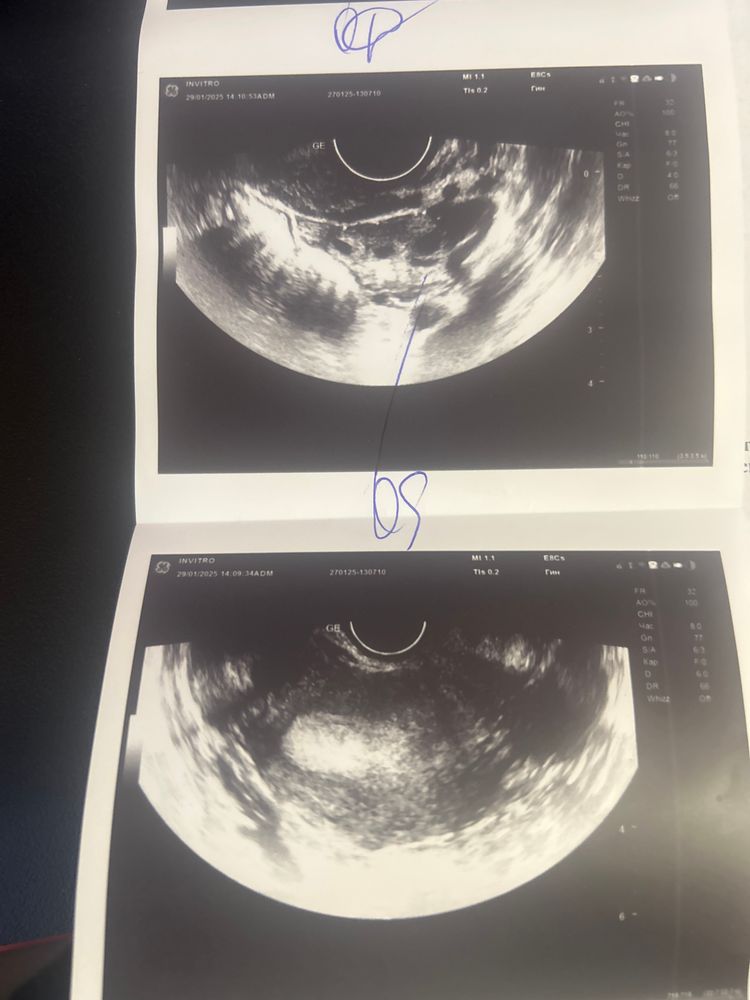

Кто-нибудь разбирается в узи? Подскажите, пожалуйста, что тут видно.

Даша, Да, есть размеры Левого яичника. и Заключение: УЗ патологии не выявлено, Желтое тело в правом яичнике, Рубец на матке.